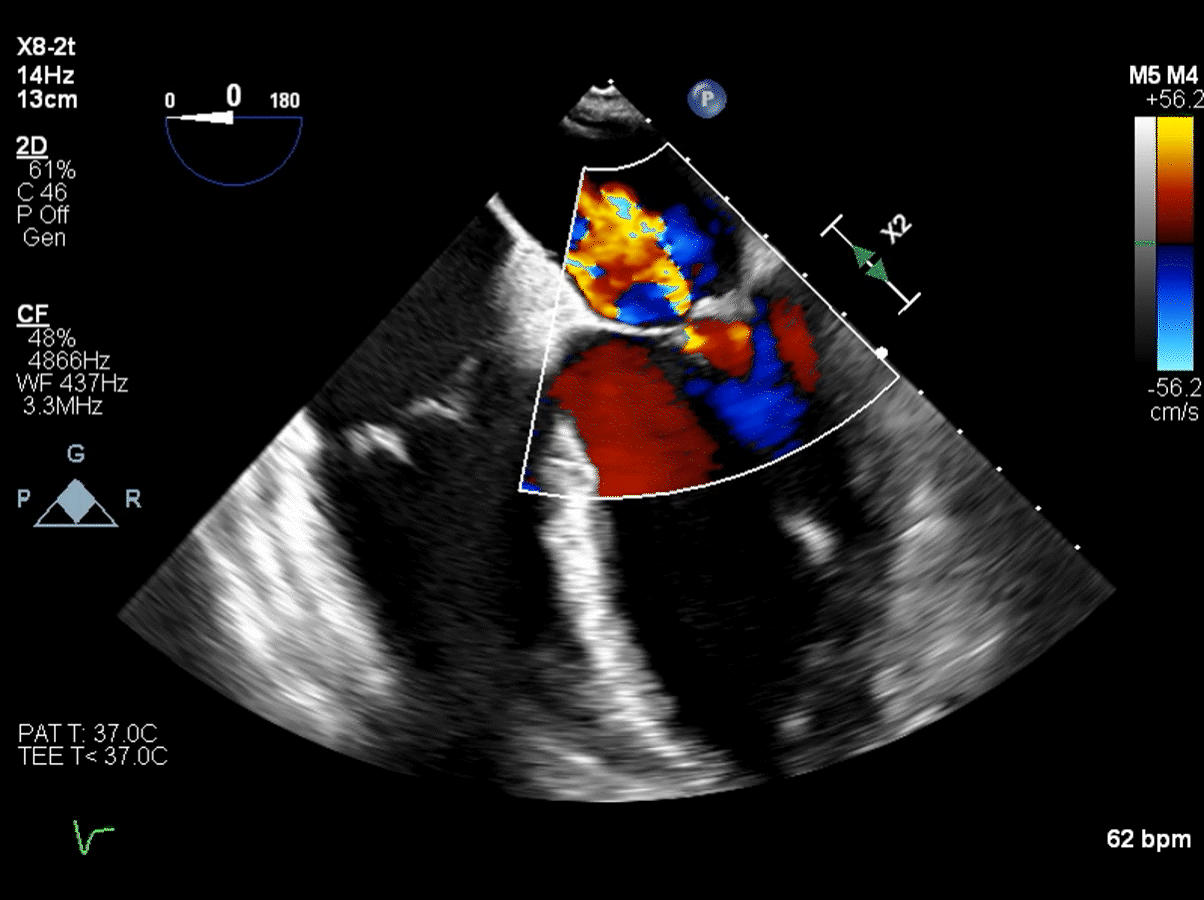

normal echocardiogram of mitral valve   echocardiogram of mitral valve with flail

With an echocardiogram, your doctor can “grade” the leak. Mitral valve regurgitation is typically graded on a scale from 0 to 4:

• 0 is no leak or very minor

• 1 is a mild leak

• 2 is a moderate leak

• 3 is a moderate to severe leak

• 4 is a severe leak

Most patients who need surgery have a grade 4 leak, or in some cases a grade 3. The valve may have a grade 2 leak for years, but it is not loud enough to be heard as a heart murmur.